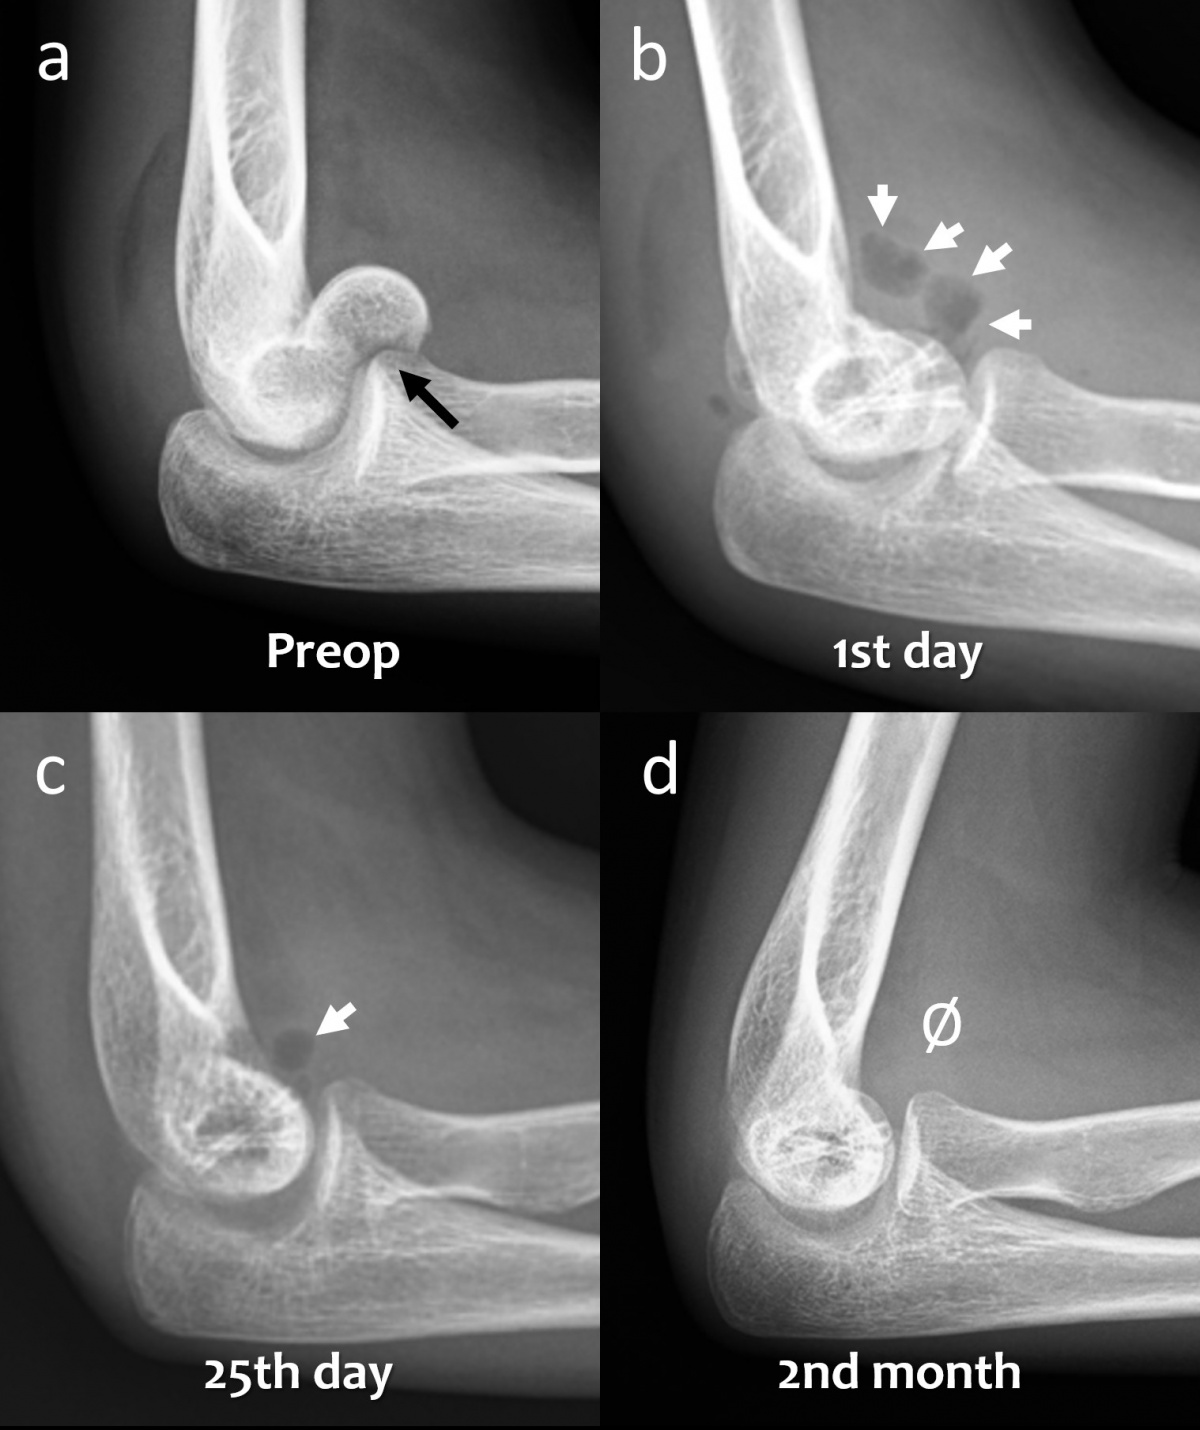

(schwarzer Pfeil) in der präoperativen lateralen Röntgenaufnahme des

Ellenbogens. (b) Röntgenaufnahme des Ellenbogens mit Gasansammlung

im Weichgewebe (weiße Pfeile) am ersten postoperativen Tag. (c)

Röntgenaufnahme des Ellenbogens 25 Tage nach der Operation, die

Gasmenge hat sich verringert (weißer Pfeil). (d) Bei der radiographischen

Nachbeobachtung nach 2 Monaten ist kein Gas im Weichgewebe

mehr sichtbar.

In frühen postoperativen Röntgenaufnahmen lässt sich auch Gas im Weichgewebe beobachten, das sich in den Gewebeschichten verteilt. Klinisch produziert dieses Gas aber keine wahrnehmbare Krepitation unter der Haut oder ähnliche Symptome. Die Gasschatten im Weichgewebe bilden sich gewöhnlich rasch zurück (Abbildung 3). In frühen postoperativen Röntgenaufnahmen stellt Gas im Weichgewebe oft ein alarmierendes Signal dar, da es – bei herkömmlichen Metallimplantaten – mit gasbildenden anaeroben Infektionen in Verbindung gebracht wird. Die Bildung von Gas während der Degradation von Mg-Implantaten hat einen vollkommen anderen Hintergrund – es handelt sich weder um eine Lockerung des Implantates noch gar um eine Infektion. Während des Abbauprozesses via Korrosion nimmt die Gasmenge zu und breitet sich im trabekulären Knochenanteil aus. Schließlich wird es jedoch vollständig resorbiert und die Mg-Schrauben zeichnen sich zunehmend prominenter ab (Abbildung 4). Tierstudien haben gezeigt, dass die Schraube schließlich durch kortikales Knochengewebe ersetzt wird (7).